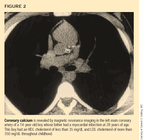

Following the recommended diet may not be sufficient for children with familial hypercholesterolemia (FH), which affects one in 500 people. Homozygotes (1:1,000,000 frequency) experience cardiovascular morbidity beginning in the second decade of life; more than half of male heterozygotes experience cardiovascular morbidity by age 50 and half of females by age 60.17 Coronary calcium, normally not recognized until the fourth decade of life, has been demonstrated in roughly 25% of adolescents with FH (Figure 2).18 Endothelial dysfunction, as assessed by brachial artery reactivity and increased carotid artery thickness as measured by ultrasound, is characteristic in adolescents with FH.19,20 Measuring cholesterol levels is a meaningful way to screen for this genetic disorder, particularly because more aggressive treatment may alter the natural history of the disease.

At what age should treatment start? What level of LDL cholesterol should trigger treatment? These questions would be easier to answer if noninvasive testing for the presence of atherosclerosis were available. For adolescents with FH, abnormalities in carotid artery wall thickness, endothelial dysfunction, and coronary calcium are indicative.18,20 These tests are not sufficiently discriminating to be used clinically, however, and we have no longitudinal studies of the impact of treatment on these secondary endpoints.